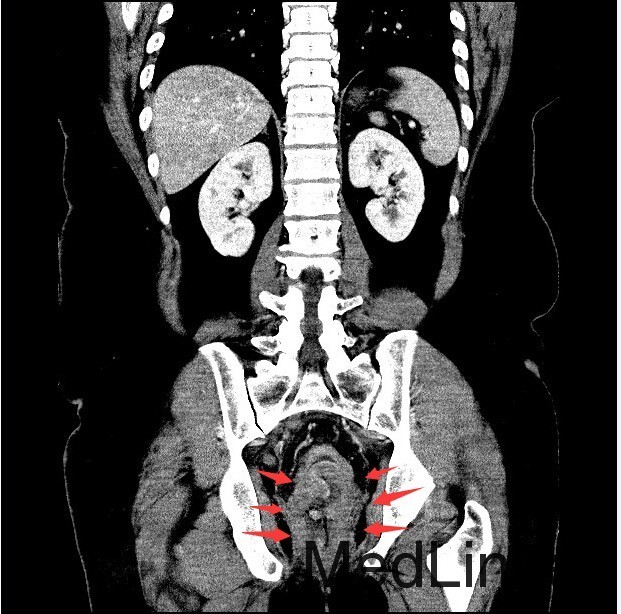

查体:肛查(KC位):肛周未见外痔,直肠指检可及环形多发内痔,部分质地较硬,有触痛,直肠壁可及多发结节,有触痛,指套退出有染血。 辅查:腹部CT示:直肠癌,累及肠壁全层,并周围肠系膜多发淋巴结转移,全身核素骨扫描结果提示:右侧坐骨轻度代谢活跃,建议定期复查以排除骨转移瘤可能,肿瘤标记物未见明显异常。肠镜示:1.直肠Ca?2.结肠息肉(已钳除)。

诊断:直肠癌? 治疗:入院后完善相关检查,肠镜活检病理示:B细胞源性非霍奇金淋巴瘤。肿瘤标记物未见明显异常。现患者要求暂缓手术治疗,办理出院。

讨论:胃肠道是原发性结外淋巴瘤最常见的累及部位。其中胃是最常见的发病部位,其次是小肠,而结肠和直肠少见。本例属于直肠淋巴瘤,属于少见肿瘤,影像表现与直肠癌相似,因此临床常常误诊为直肠癌,本例即误诊为直肠癌。影像学上只要认真观察一般能通过以下几点将两者鉴别开:淋巴瘤一般累及的肠段较长,肠壁较厚,肠腔变窄不明显,呈动脉瘤样扩张,没有肠梗阻表现,周围脂肪界面清晰。而大肠癌则相对较局限,常伴有肠腔的狭窄及肠梗阻的表现,而且常通过浆膜直接向周围浸润,周围脂肪间隙模糊。只要认真寻找这些影像征象,还是能够将两者较好的区别开来。